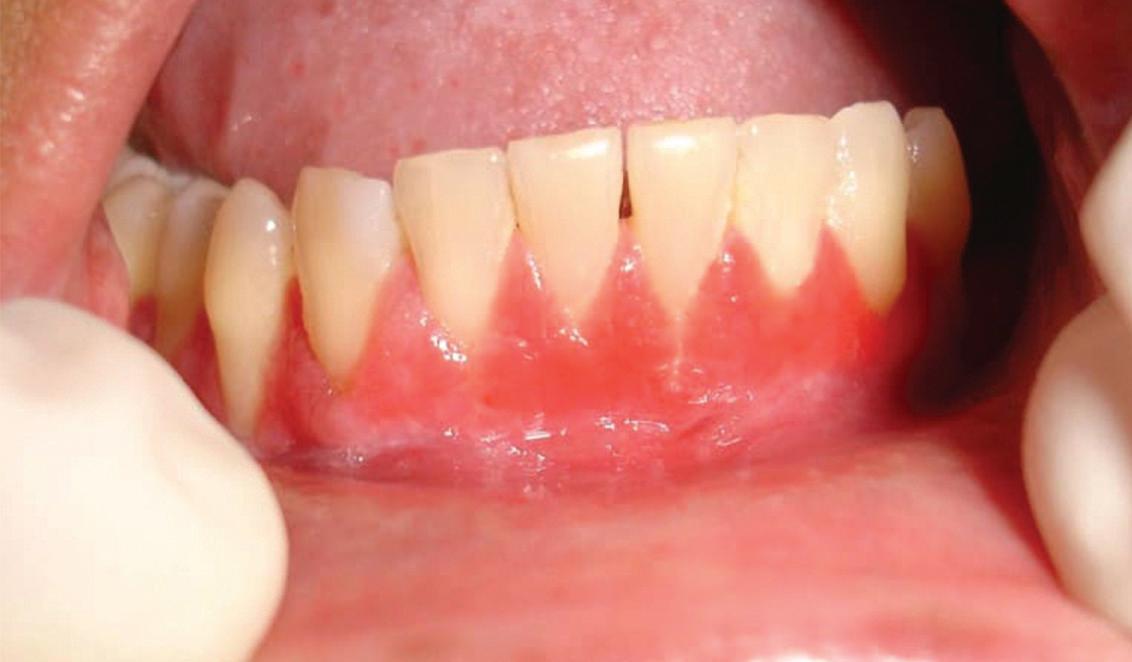

48 Oral Medicine, Oral Diagnosis, Oral Pathology

Multidisciplinary approach to diagnosis and management of lymphadenopathy in a patient with mucous membrane pemphigoid: a case report

Heba Turkstani

Eric T. Stoopler

Temitope T. Omolehinwa

Eman Alamodi

Mel Mupparapu